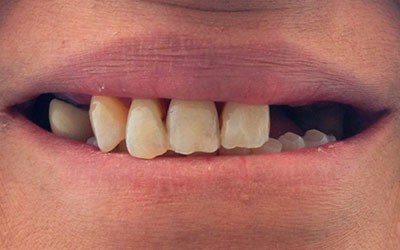

Por otro lado, este tipo de rehabilitación también está indicada en aquellas personas que, aunque aún mantienen dientes en la boca, dichas piezas dentales presentan un pronóstico imposible a corto plazo y están abocados al edentulismo total.

Antes de comenzar a fabricar la prótesis es necesario realizar un completo estudio del caso concreto de cada paciente, para asegurarnos de que ésta se ajusta completamente a sus necesidades (en todo lo relativo a color, tamaño, comodidad, etc).